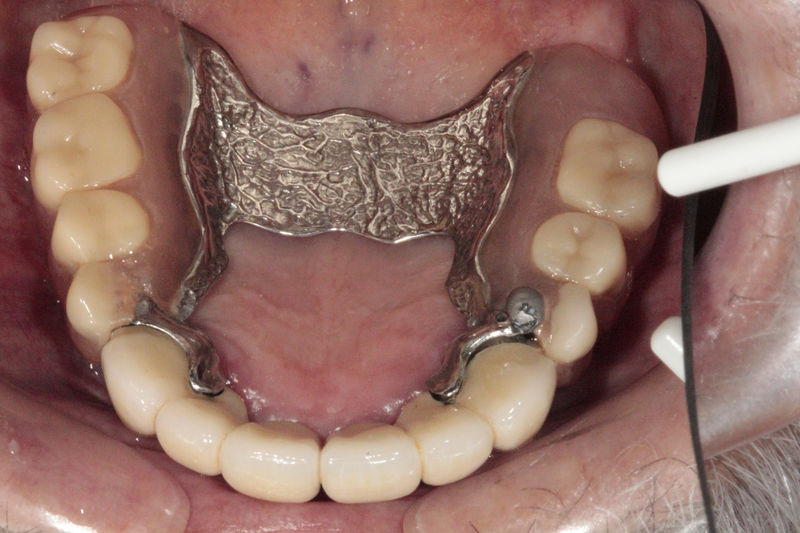

Las prótesis dentales son aparatos o dispositivos que se utilizan para reemplazar los dientes ausentes y las estructuras orales relacionadas.

Restauraciones fabricadas en el laboratorio los cuales se usan para reemplazar dientes ausentes usando dientes, coronas y/o tejidos blandos como soporte y que pueden y deben de ser removidas para su limpieza. Para poder enviar el caso al laboratorio se toman impresiones utilizando materiales de impresión o técnicas modernas digitales.

Restauraciones fabricadas en el laboratorio los cuales se usan para reemplazar dientes ausentes en toda una arcada usando implantes y/o tejidos blandos como soporte y que pueden y deben de ser removidas para su limpieza. Para poder enviar el caso al laboratorio se toman impresiones utilizando materiales de impresión o técnicas modernas digitales.

Implante fracasado, extracción, carillas, coronas y prótesis fija.